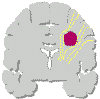

Un glioma può essere quindi distinto in tre tipi (Daumas-Duport): |

Tipo

I: lesione circoscritta |

II: lesione compatta ed area di tessuto cerebrale infiltrato |

III: lesione diffusa con parenchima infiltrato |